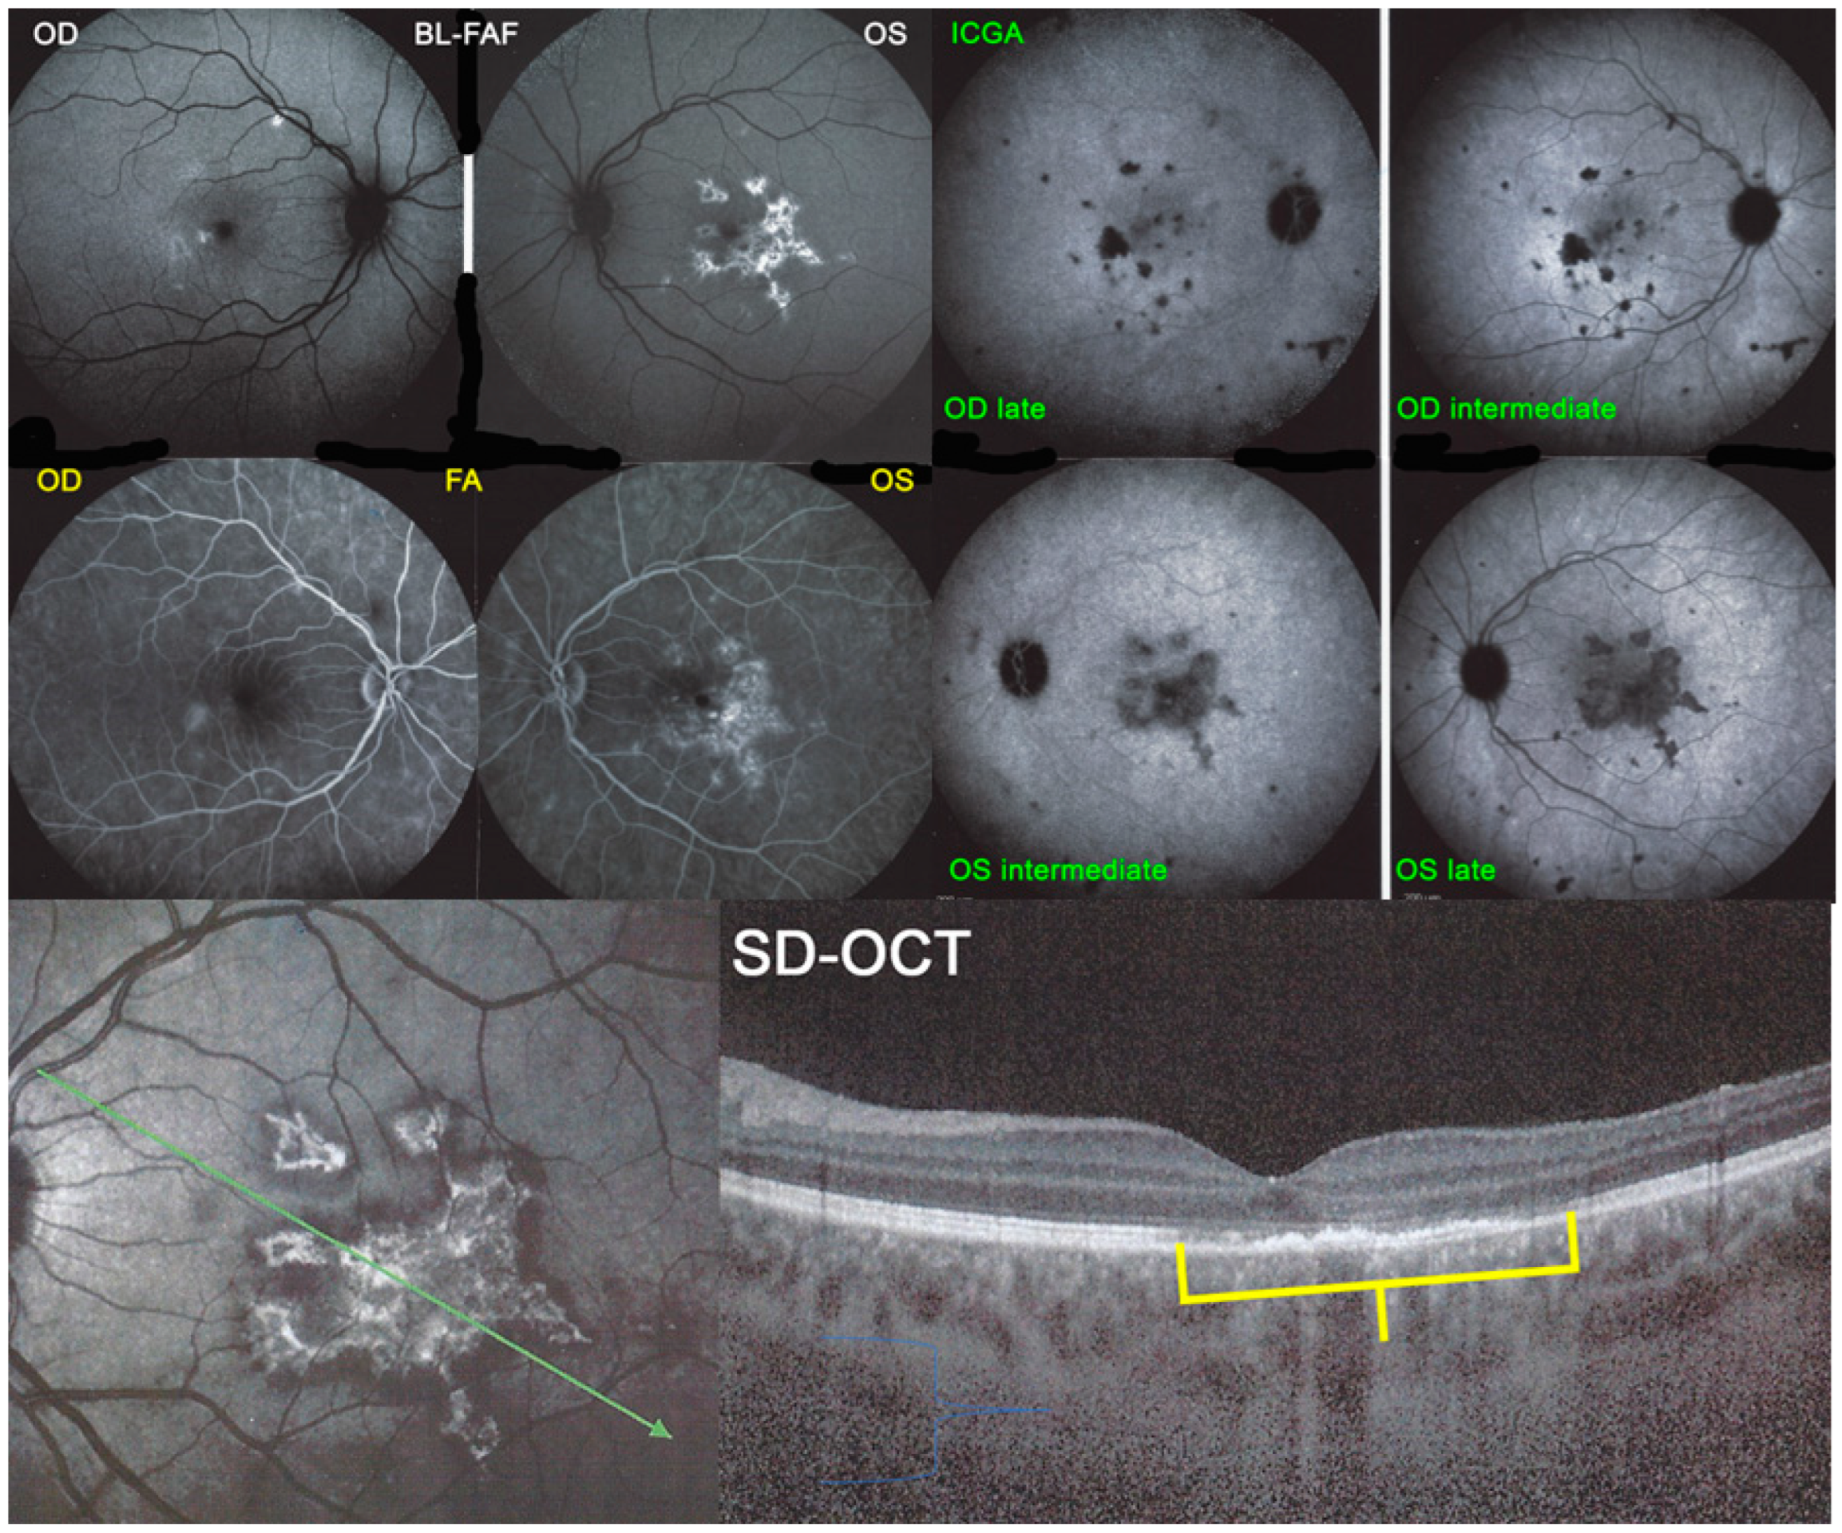

Figure 5. APMPPE/AMIC; FA & ICGA & BL-FAF at presentation. Case of acute APMPPE/AMIC analysed by ICGA & FA & BL-FAF. This multimodal imaging shows that the initial event is choriocapillaris non-perfusion clearly shown by extensive areas of ICGA hypofluorescence (middle two frames) while retinal (FA) involvement is still limited. BL-FAF hyperautofluorescence is still limited as choriocapillaris non-perfusion induced ischaemia did not alter the outer retina yet, except in a few areas along the superior temporal arcades.

Figure 24. APMPPE/AMIC; BL-FAF. ICGA, FA & SD-OCT findings in a case in subacute stage having received prednisone therapy for 10 days: BL-FAF (top left two frames) shows areas of hyperautofluorescence (OS > OD) corresponding to the areas of hypofluorescence (choriocapillaris non-perfusion) on ICGA (top right quartet of frames). FA (middle left two frames) shows areas of staining (OS) most probably produced by exudation of retinal vessels in response to outer retinal ischaemia. SD-OCT (bottom two pictures) shows loss and disorganisation of photoreceptor outer segments, disrupted RPE layer with overlying hyperreflective focal deposits in correspondence to hyperautofluorescence.

For precise evaluation of areas of choriocapillaris non-perfusion and their follow-up, ICGA is by far the most valuable modality, revealing discrete to large areas of scattered or confluent hypofluorescent dark areas present from early to late angiographic frames [22,23,24] (Figure 4a,b and Figure 5).

Blue light fundus autofluorescence (BL-FAF) shows both hyperautofluorescence and hypoautofluorescence depending on the stage of evolution of the disease and is sometimes difficult to interpret. In the very acute stage, there are still limited areas of hyperautofluorescence following the loss of photoreceptor outer segments due to non-perfusion which has caused ischaemia without chorioretinal atrophy. In the subacute stage, there is an alternation of hyperautofluorescence either due to loss of photoreceptor outer segments or damage of RPE cells with accumulation of fluorophore debris, or hypoautofluorescence due to chorioretinal atrophy with loss of RPE [5,7,25] (Figure 6 and Figure 7a,b). In progressing lesions hypoautofluorescence is central (atrophy) and hyperautofluorescence is located in the periphery of lesions where ischaemia causes photoreceptor outer segment loss with still conserved RPE and/or RPE cells with accumulation of cellular fluorophore debris (Figure 7a,b).

The exact extensions of bilateral lesions were clearly delineated on ICGA showing scattered small hypofluorescent areas of choriocapillaris non-perfusion OD and more confluent hypofluorescent lesions OS (Figure 24), corresponding to areas of hyperautofluorescence on BL-FAF and FA hyperfluorescence (Figure 24). SD-OCT showed loss of photoreceptor outer segments and irregularity of the IS/OS line due to ischaemia following choriocapillaris non-perfusion (Figure 24). FA hyperfluorescence is explained by compensatory retinal exudation with limited pooling as the patient was already under corticosteroid therapy. Besides choriocapillaris non-perfusion, the whole choroidal thickness was increased (Figure 25).